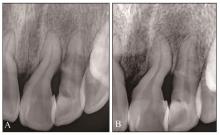

图 8

术后根尖片A:术后15个月;B:术后 18个月。"